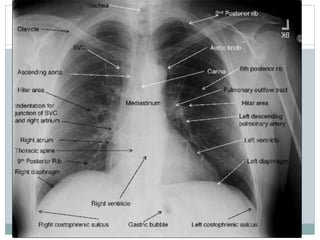

Avaliação Do Mediastino

 Mediastino

Superior

Inferior

 Traqueia

 Bronquios

 Angulos

Costofrenicos/

cardio

 Pulmões

Costelas

POST ANT

Diafragma

pneumoperitoneo